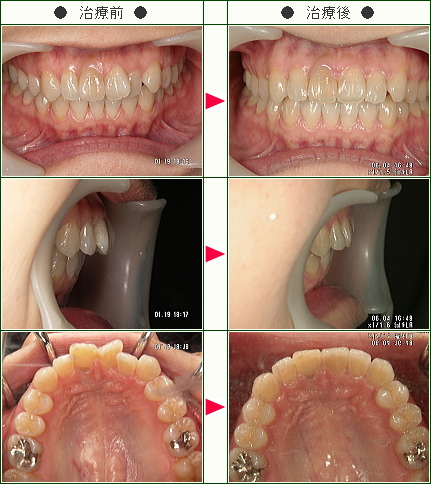

☆歯のデコボコ矯正症例(Y・S様 36歳 女性)